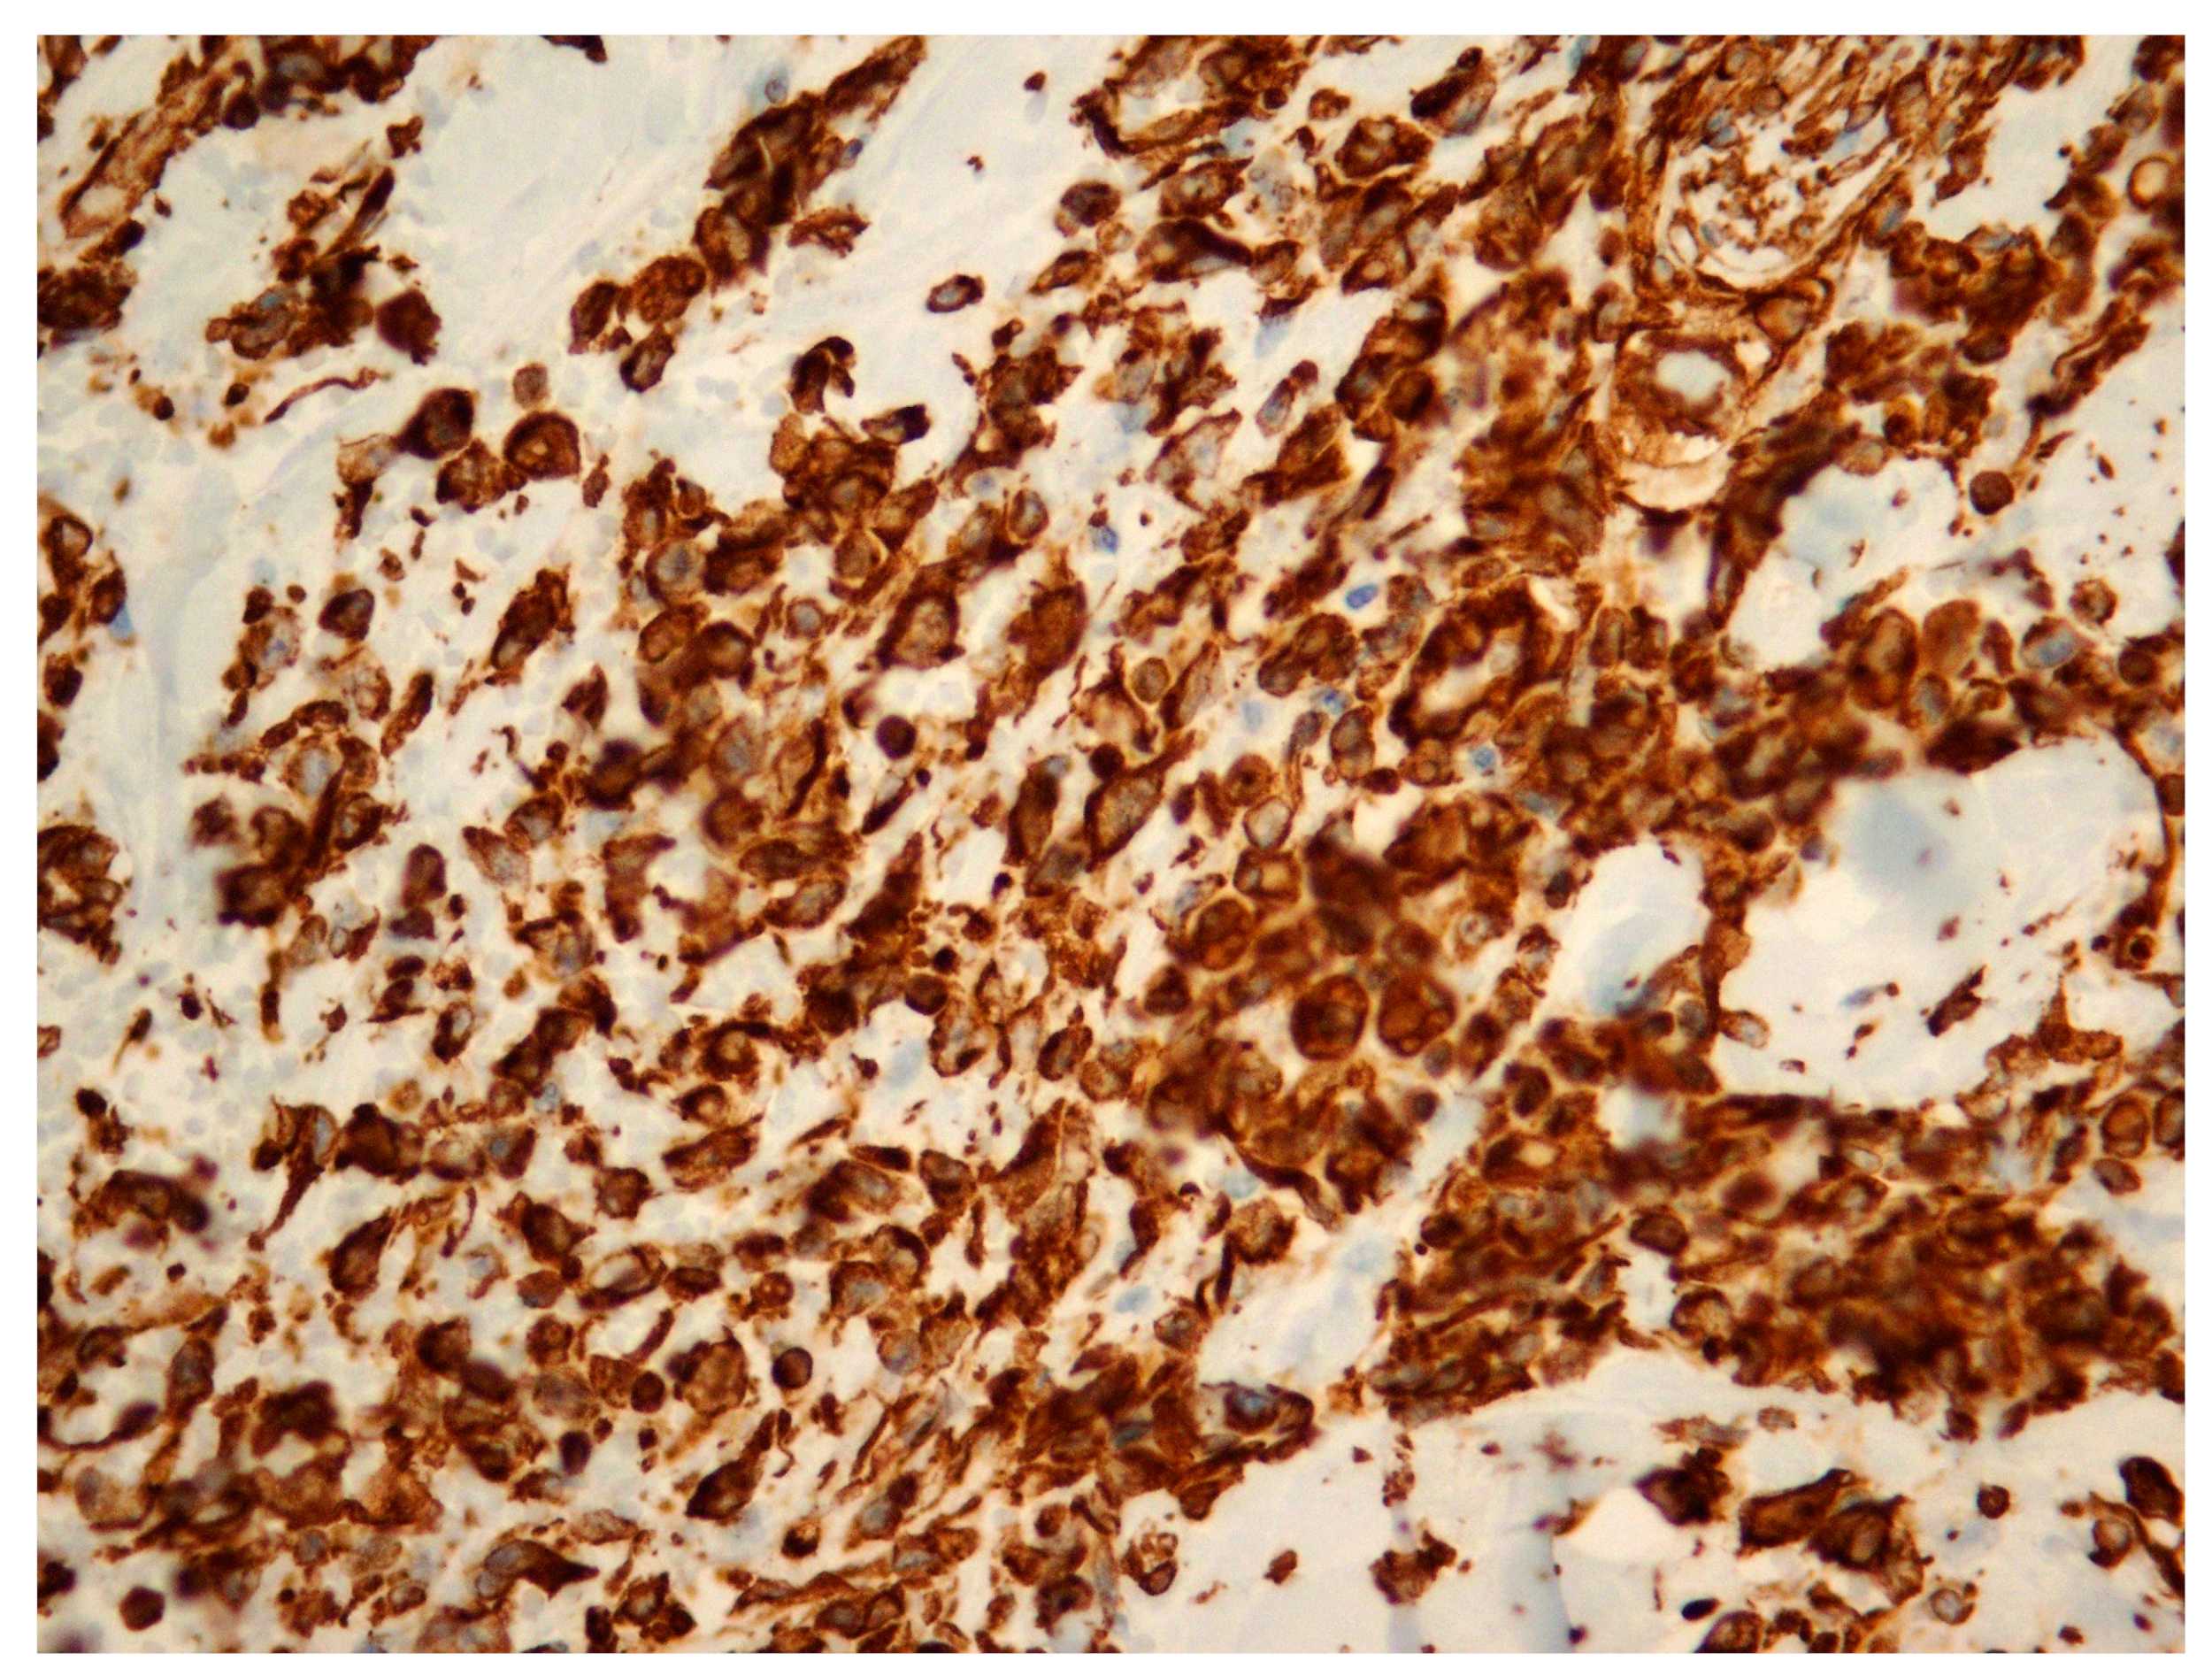

Figure 1, Figure 2 and Figure 3 show the RIBAS clinical presentation and pathology results. Detailed RIBAS clinical presentations and treatment strategies are summarized in Table 2 and Table 3. No patient had active BC at the time of RIBAS diagnosis, nor did any patient develop recurrent BC during the RIBAS follow-up. Median age at RIBAS diagnosis was 64 (range: 36–68) years, while the estimated median time from BC RT to RIBAS diagnosis was 64 (95% CI > 57) months. Mean tumor size at RIBAS diagnosis was 55 (SD 32.78) mm. All nine patients had localized disease and underwent total mastectomy with curative intent. Four patients needed pectoral defect reconstruction. A total of four patients received adjuvant chemotherapy, three of whom received doxorubicin as monotherapy, while the remaining patient had doxorubicin and cyclophosphamide combination (AC protocol). The patients were followed up for a median of 30 (range: 7–40) months after the initial RIBAS operation. Local recurrence was observed in seven patients, five of whom had surgery with curative intent. Three patients developed distant metastases during follow-up.

Figure 3. Radiation-induced breast angiosarcoma—microscopic analysis, Vimentin staining, 40 × 1.